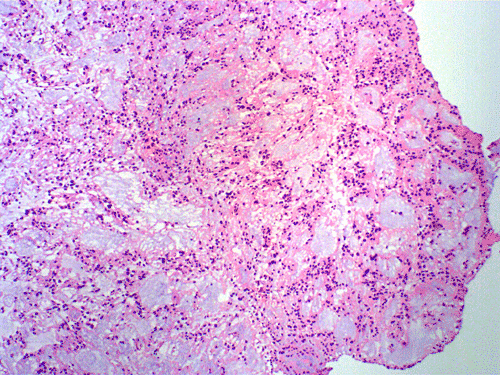

Clinical informationThe patient was a 40 year-old man with back pain for a long but unknown duration of time. MRI revealed a sharply circumscribed, lobulated, brightly enhancing, 3 cm mass in the cauda equina. The mass was removed and the followings are representative photomicrographs from the specimen. Panel A to C are taken from intraoperative cytologic preparation, D and E are taken from frozen section, F to H are taken from permanent sections.

On cytologic preparations, there are clumps of tissue that do not smear out well (Panel A). On higher magnification, these tissue clusters are composed of large blobs of bluish, acellular, mucoid material admixed with cells with relatively uniform, bland nuclei and small amount of cytoplasm (Panel B). In the less tightly packed areas, the long cytoplasmic processes of the cells can be well appreciated (Panel C). These long processes are highly suggestive of a glial neoplasm. On frozen sections, the lesion is composed of multiple blobs of bluish, mucoid material surrounded by tumor cells (Panel D and E). Features of the paraffin sections are not that much different from that of the frozen sections (Panel F G H).